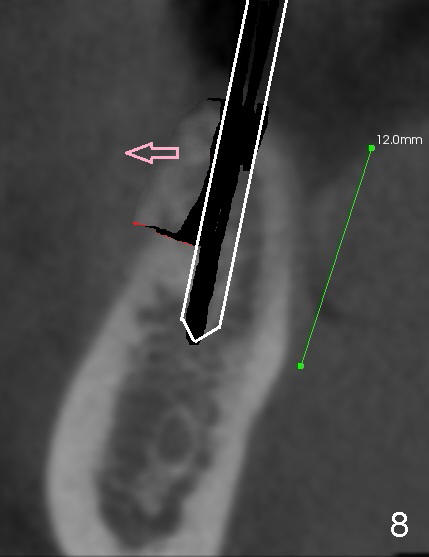

The patient is scheduled to return for implant placement 3 weeks later. The red lines in Fig.4 (CT coronal section) represent bony cuts in the ridge. A transverse incision is made over the top of the ridge with minimal exposure of the ridge. A curved osteotome is inserted into the upper bony cut (Fig.5). As the chisel is tapped in, the buccal segment moves buccally (Fig.6 pink arrow). When the chisel is withdrawn, a pilot drill is used to initiate osteotomy (Fig.7). As drills increase in diameter, the buccal segment continues moving buccally (Fig.8). Finally a bone-level implant (4.1 or 4.5x12 mm, Fig.9) or sub-crestal implant (4 or 4.5x8) is placed. Will the ridge split work?